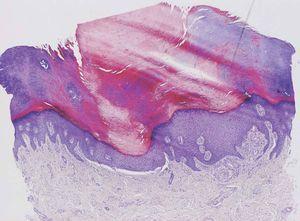

Se practicó una biopsia del borde activo de una de las placas de las caderas, observando un infiltrado linfohistiocitario en la unión dermo-epidérmica con vacuolización de la basal y queratinocitos necróticos a distintos niveles en la epidermis. También se observó un infiltrado perivascular-perianexial con reducción de las estructuras anexiales (fig. 3). Esta biopsia era compatible con el diagnóstico de DM.

Figura 3. Biopsia del margen activo de placa en cadera. Dermatitis de interfase con vacuolización parcheada de la basal y queratinocitos necróticos, infiltrado perivascular y perianexial en dermis (hematoxilina-eosina, x40).